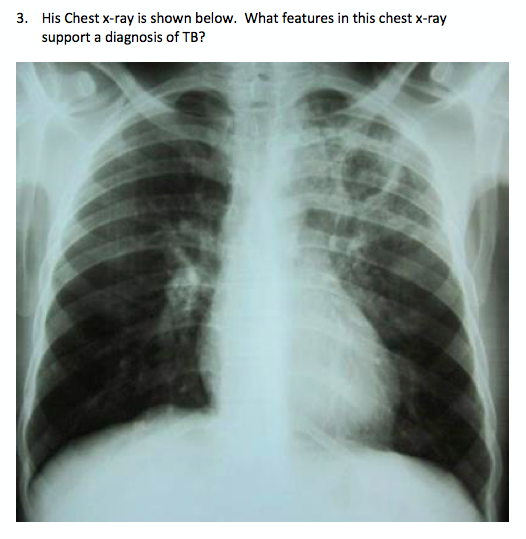

What features in this history supports the diagnosis of pulmonary tuberculosis?

Tiredness

Weight loss

Fever

Cough

Haemoptysis

Diabetes

Left upper zone

Consolidation/shadowing in left upper zone